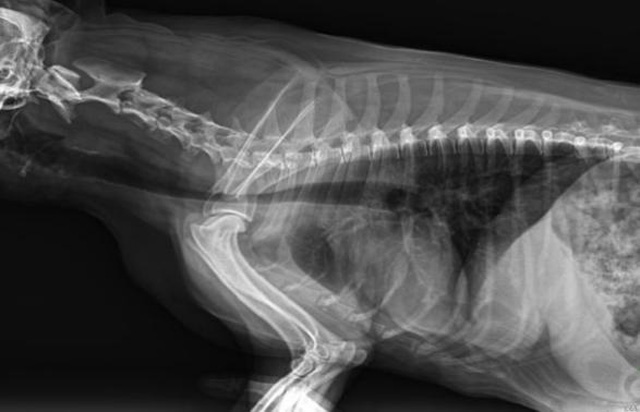

從臨床角度出發(fā),大力發(fā)展動(dòng)態(tài)DR,以精準(zhǔn)的診斷為小動(dòng)物保駕護(hù)航。寵物DR升級(jí)使用雙焦點(diǎn)球管,大尺寸平板探測(cè)器,超高頻逆變高壓發(fā)生器。醫(yī)用纖維板臺(tái)面,防止寵物劃傷。寵物DR整機(jī)小巧實(shí)用,骨略結(jié)構(gòu)和器官位置,分類詳細(xì),運(yùn)算更快,讓拍攝條件更科學(xué),有助于提高診斷的準(zhǔn)確性和效率。安裝移動(dòng)非常方便。低輸入電流設(shè)計(jì),220伏常規(guī)電壓。多品種動(dòng)物程序設(shè)定,滿足各個(gè)臨床需求。成像效果顯著,寵物不能言語(yǔ)表達(dá),導(dǎo)致誤診率居高不下。寵物診療均以經(jīng)驗(yàn)診斷為主的方式,確保最小化輻射降低對(duì)醫(yī)生及動(dòng)物的影響。以滿足精細(xì)化的寵物醫(yī)療需求,成為診斷寵物內(nèi)外科疾病的必備工具。使醫(yī)院更有競(jìng)爭(zhēng)力,為醫(yī)院創(chuàng)收增光添彩。

寵物DR的操作流程是什么呢?第一步首先插上整機(jī)電源,然后按下主機(jī)電源。打開(kāi)高壓發(fā)生器的電源,工作站主機(jī)電源。等待主機(jī)軟件的自動(dòng)啟動(dòng)。通過(guò)軟件登記檢查的寵物信息,選擇寵物檢查拍攝部位。調(diào)節(jié)限速器拍攝區(qū)域。關(guān)閉鉛房門,點(diǎn)擊開(kāi)始拍攝按鈕。拍攝完成調(diào)整圖像并且輸出。